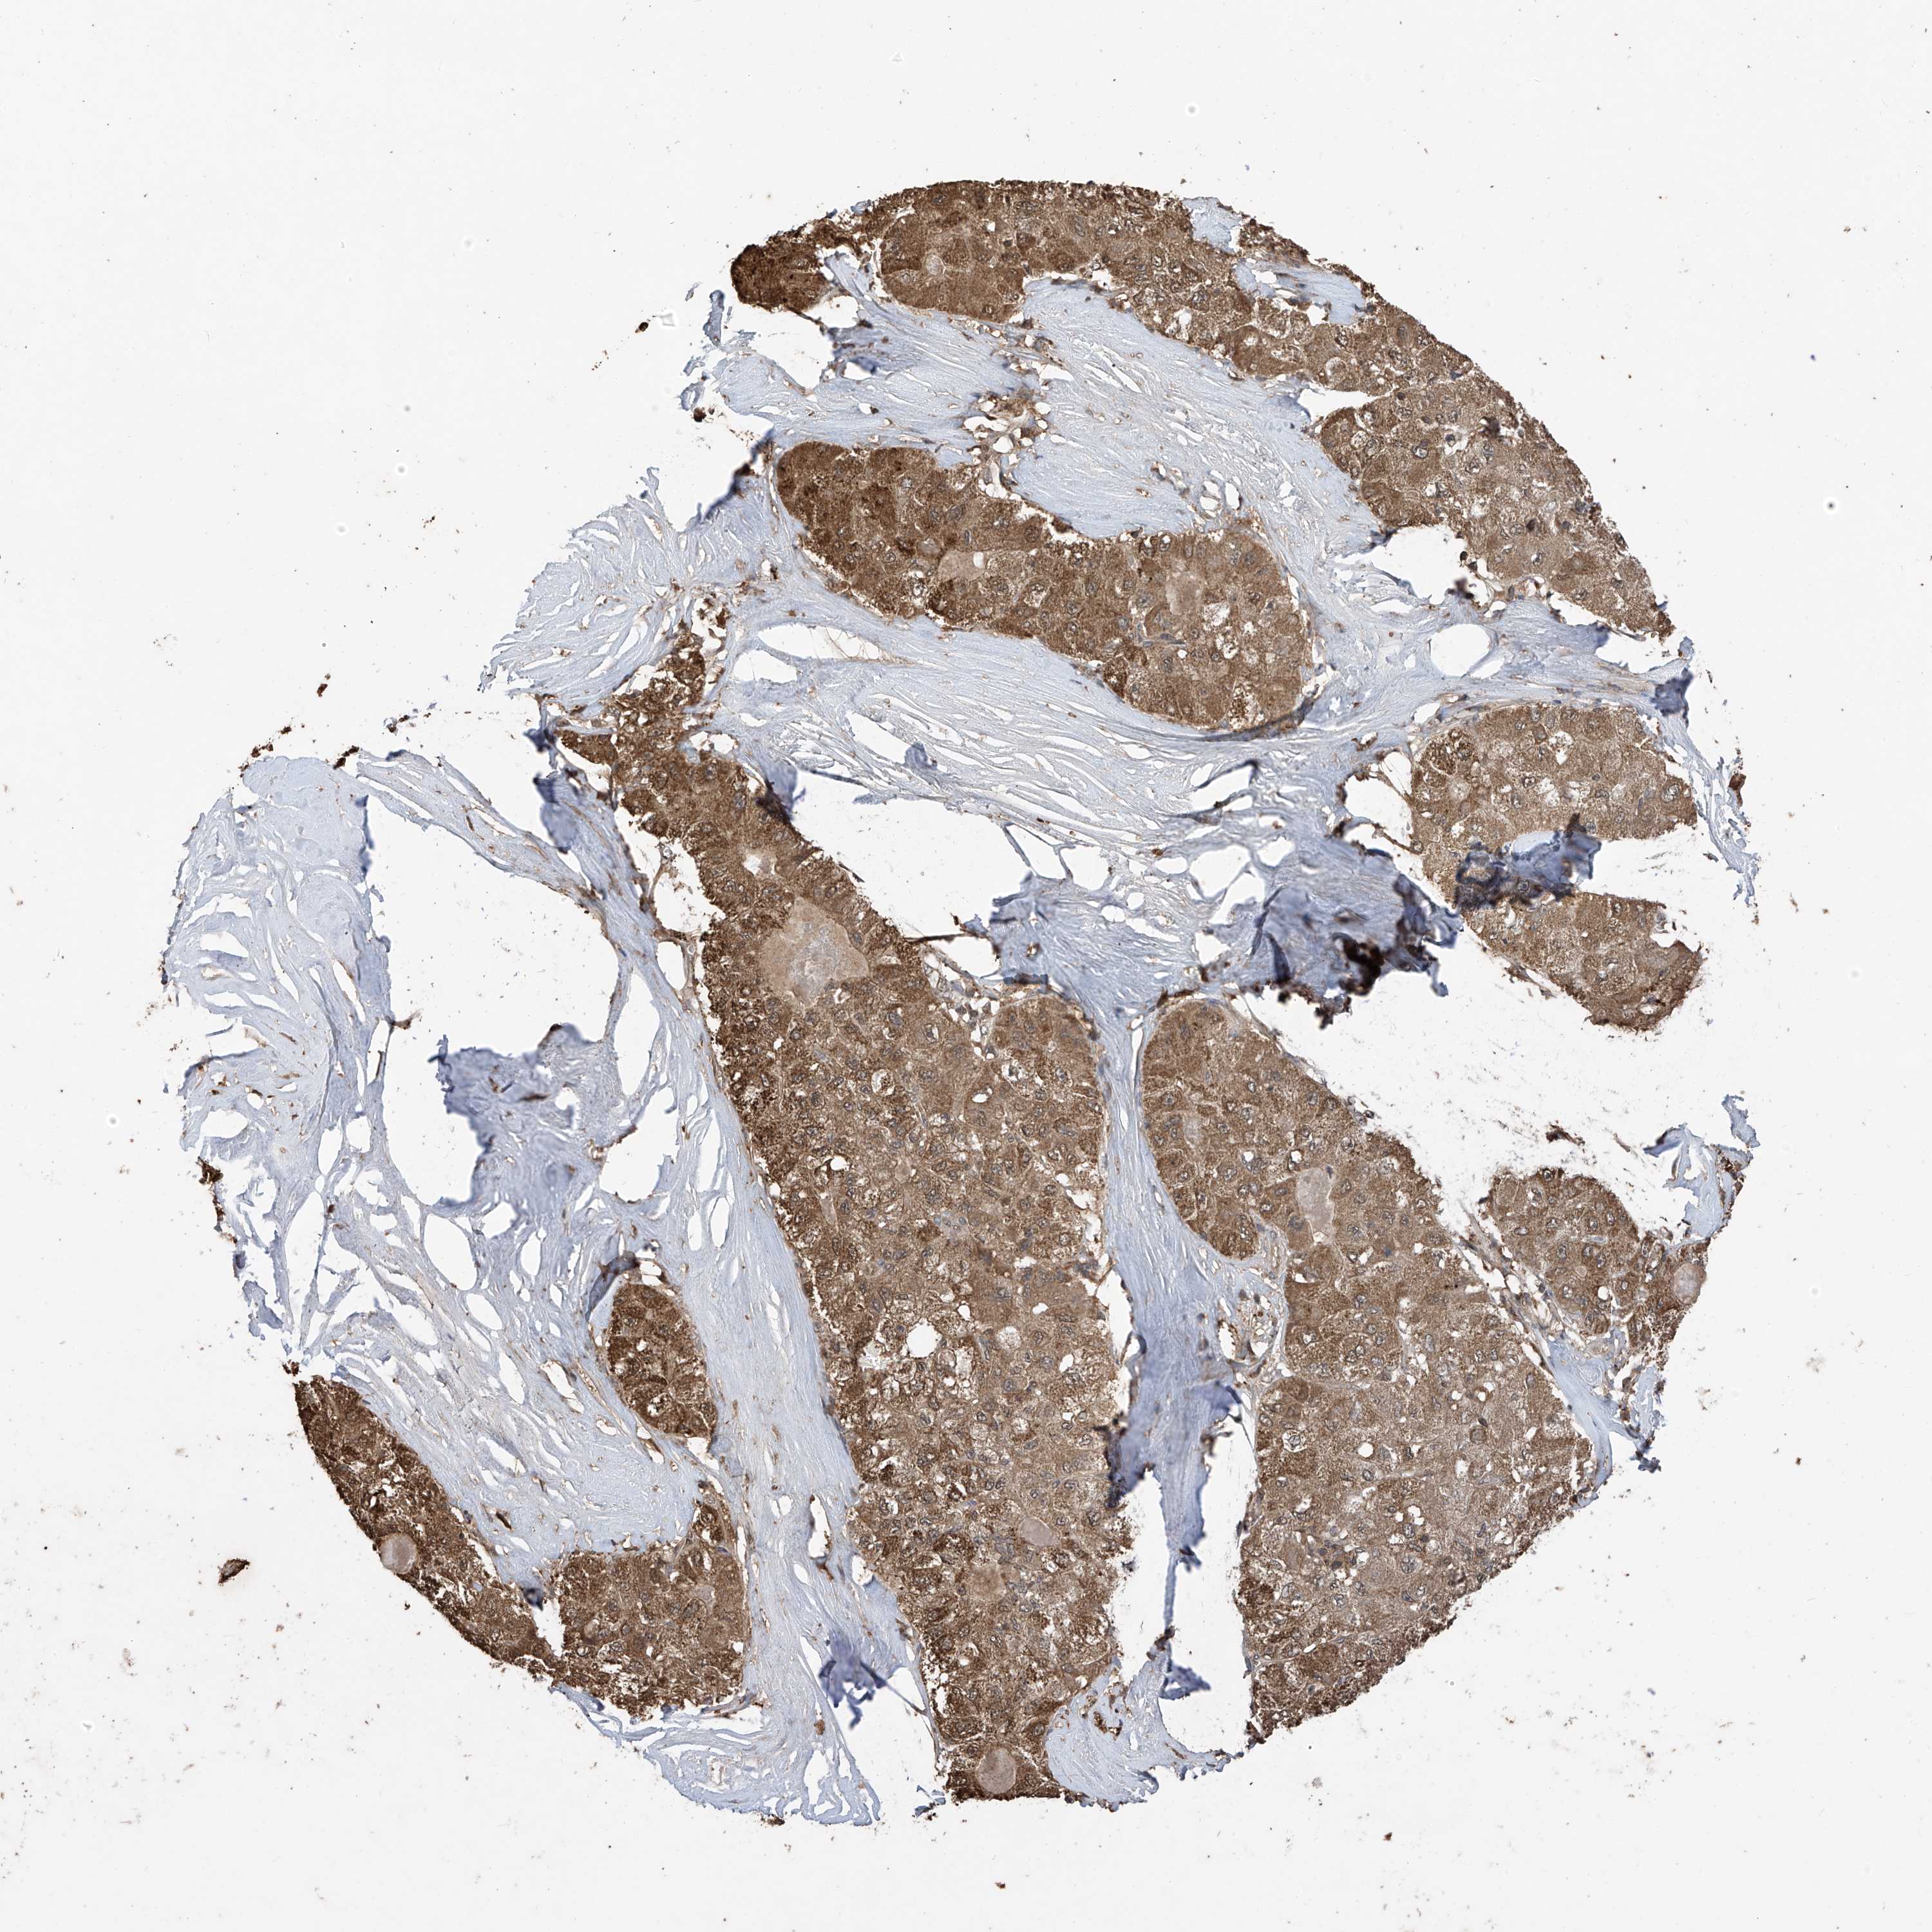

LIVER CANCER - Protein expressioni

A mouse-over function shows sample information and annotation data. Click on an image to view it in a full screen mode. Samples can be filtered based on level of antibody staining by selecting one or several of the following categories: high, medium, low and not detected. The assay and annotation is described here.

Note that samples used for immunohistochemistry by the Human Protein Atlas do not correspond to samples in the TCGA dataset.

Antibody stainingi

Antibody staining in the annotated cell types in the current human tissue is reported as not detected, low, medium, or high, based on conventional immunohistochemistry profiling in selected tissues. This score is based on the combination of the staining intensity and fraction of stained cells.

Each image is clickable and will lead to virtual microscopy that enables deeper exploration of all samples and also displays staining intensity scores, fraction scores and subcellular localization as well as patient and tissue information for each sample.

Antibody HPA034602

Antibody HPA034603

Antibody CAB033424

Staining

High

Medium

Low

Not detected

Intensity

Strong

Moderate

Weak

Negative

Quantity

>75%

75%-25%

<25%

None

Location

Nuclear

Cytoplasmic/membranous

Cytoplasmic/membranous,nuclear

Cholangiocarcinoma

Carcinoma, Hepatocellular, NOS